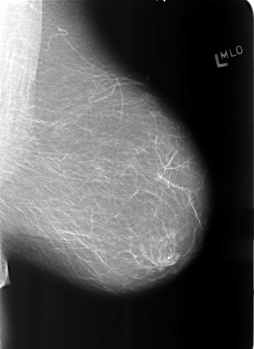

B_3365_1.LEFT_MLO

LEFT_MLO LINES 5584 PIXELS_PER_LINE 4064 BITS_PER_PIXEL 12 RESOLUTION 50 NON_OVERLAY

LESION_TYPE CALCIFICATION TYPE PLEOMORPHIC DISTRIBUTION CLUSTERED

LESION_TYPE MASS SHAPE IRREGULAR MARGINS ILL_DEFINED

ASSESSMENT 4

SUBTLETY 4

PATHOLOGY BENIGN